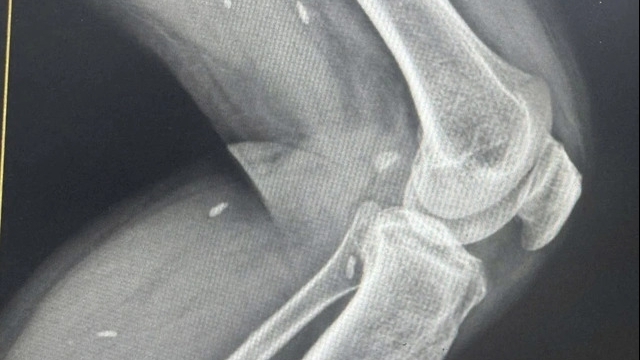

| Các bác sĩ khoa Phẫu thuật Nhiễm khuẩn, Bệnh viện Hữu nghị Việt Đức phẫu thuật cho 1 người bệnh. Ảnh: BVCC |

Ca bệnh thứ 2 là trường hợp bệnh nhân Hà V T. (Nam, 57 tuổi) ở Thanh Sơn, Phú Thọ. Cách đây 1 tuần, ông T có nhọt nhỏ ở vùng nách bên trái. Bệnh nhân đã tự ý ở nhà đắp thuốc nam. Từ một nhọt nhỏ, cả vùng và ngực bên trái của bệnh nhân đã bị viêm tấy lan tỏa và hoại tử. Các bác sĩ Bệnh viện Hữu nghị Việt Đức đã cắt lọc, để hở vết thương, dùng kháng sinh mạnh và thay băng thường xuyên bằng những băng đặc biệt cho bệnh nhân.